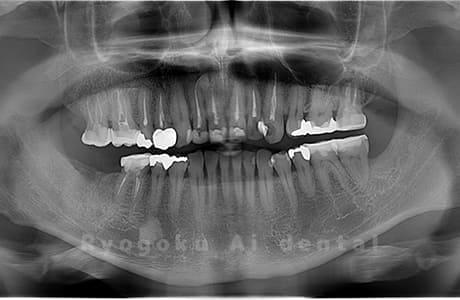

Case02

-

- 原因

- 下顎の水平埋伏智歯

- 治療内容

- 下顎の水平埋伏智歯を抜歯

<リスク・副作用>

手術後は痛み、腫れ、痺れなどの副作用が生じる場合があります。